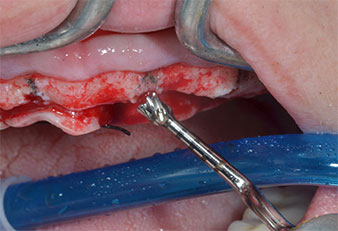

Ein flammenförmiges, diamantiertes piezochirurgisches Instrument (Piezomed I1) wurde verwendet, um die Implantatpositionen zu markieren und die Pilotpräparationen durchzuführen (Abb. 3). Dabei wurde darauf geachtet, eine Auf- und Abbewegung mit reduzierter Leistung, voller Spülung und niedrigem Druck (unter 300 g) anzuwenden. Als Nächstes wurde ein Pilotinstrument (Piezomed I2A/I2P) zur initialen Erweiterung der Implantatlager auf einen Durchmesser von 2 mm verwendet (Abb. 4), gefolgt von einem 3-mm-Instrument (Abb. 5).

Bei dichtem Knochen sollte das gesamte Set, einschließlich der Zwischeninstrumente Piezomed Z25P und Z35P verwendet werden, um die Osteotomien vor dem nächsten Schritt zu erweitern.

Diese Instrumente sind auch für die Aufbereitung bei interner Sinusbodenaugmentation in der Nähe der Sinusmembran indiziert oder wenn weniger als 4 mm Restknochenhöhe verbleibt.

Im vorliegenden Fall wurden die Instrumente Z25P und Z35P wegen des relativ weichen posterioren Knochens nicht verwendet, der problemlos mit dem I3A/I3P bearbeitet werden konnte.